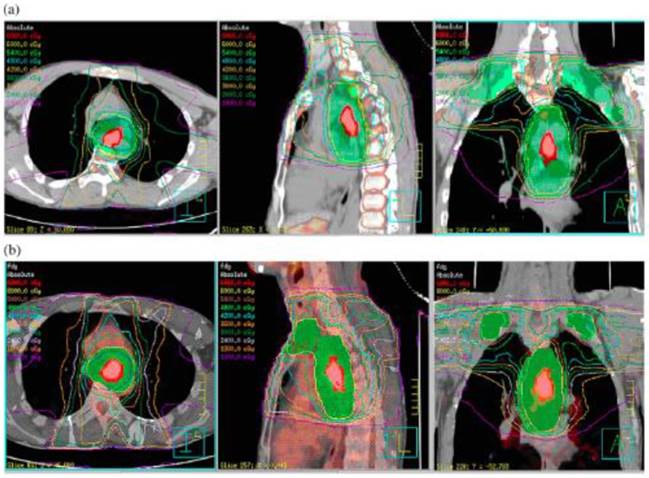

Radiation therapy for esophagus cancer. The standard of care for esophageal cancer is chemotherapy and radiation together followed by surgical evaluation. If the cancer is in the part of the esophagus near the stomach, chemo without radiation may be given before surgery. With external radiation, the patient lies on a table while a radiation therapist directs precisely controlled energy waves directly at the tumor.

The machine used in external beam therapy is called a linear accelerator. The upper thoracic esophagus extends from the thoracic inlet to the inferior border of the azygous vein. Radiation therapy for esophageal cancer.

The nonsurgical treatment for localized, deeply invasive esophageal cancer has been external beam radiation therapy (ebrt) and concurrent chemotherapy. Our radiation oncologists have years of experience safely and effectively treating esophageal cancer with radiation. The middle thoracic esophagus extends from.

The main type of radiation therapy used in esophageal cancer treatment is external beam therapy. Until 1956 orthovoltage roentgen rays were the only radiation modality available for this disease.